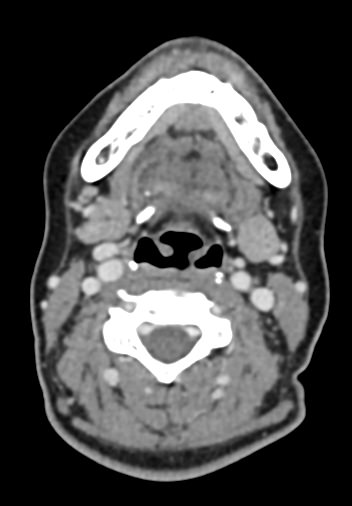

Оптимальным методом обследования гортани и голосовых связок является мультиспиральная компьютерная томография. Метод позволяет подробно визуализировать состояние данной анатомической области и выявить патологические изменения, которые незаметны при ларингоскопии (визуальный осмотр гортани с помощью специальных инструментов), проведении УЗИ и обычной рентгенографии.

Компьютерная томография позволяет оценить состояние костного скелета гортани и особенно важна в оценке состояния хрящей гортани, которые лучше всего визуализируются с помощью данного исследования. В частности, мультиспиральная КТ позволяет выявить распространение рака гортани в ткань щитовидного хряща и другие окружающие структуры.

При подозрении на опухоль гортани нативная мультиспиральная КТ дополняется проведением внутривенного болюсного контрастирования. Для этого пациенту внутривенно вводится контрастный препарат на основе йода.

Контраст хорошо накапливается в патологически измененных участках, за счет этого становятся отчетливо видны на снимках их границы, размеры, точная локализация относительно окружающих здоровых тканей. По характеру накопления контраста можно отличить доброкачественные опухоли от злокачественных, определить степень распространенности процесса, выявить поражение регионарных лимфатических узлов.

На полученных снимках можно оценить состояние всех структурных элементов гортани, голосовых складок, хрящей, а также лимфатических узлов, сосудов и шейных позвонков на исследуемом уровне. Инновационные возможности аппаратов позволяют построить 3D-модель зоны исследования, которая дает наглядную картину пространственного расположения органов, что бывает особенно важно при планировании хирургических операций.